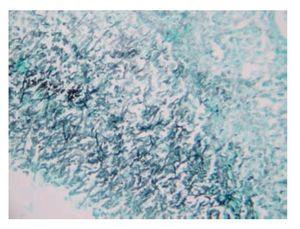

Figura 1. Zona de infarto hemorrágico en parénquima pulmonar rodeada por abundantes hifas de Aspergillus (H.E., 10x).

El análisis de la pieza quirúrgica de la hemicolectomía derecha mostró necrosis isquémica hemorrágica perforada en ciego con infiltrado de abundantes neutrófilos. Había úlceras de fondo necrótico con edema y congestión vascular en la mucosa cecal vecina a la zona de necrosis y en la mucosa del íleon distal. No se identificó ningún agente infeccioso. La autopsia reveló casi 2 litros de líquido de ascitis turbio y de color café. El hígado pesaba 1 400 g, estaba aumentado de tamaño, con una zona extensa de necrosis en el lóbulo derecho de 14 cm de diámetro. La luz de la vena hepática derecha y sus ramas estaban ocluidas por completo por un trombo y en los cortes histológicos la pared estaba infiltrada con neutrófilos. Por medio de las tinciones de hematoxilina y eosina y de Grocott, se identificaron escasas hifas septadas, bifurcadas en ángulo agudo, que por sus características morfológicas correspondían a Aspergillus. No había trombosis de la vena porta. En el parénquima del lóbulo hepático derecho existía necrosis hemorrágica confluente, panlobulillar, en la que se identificaban escasos hepatocitos residuales en el área periportal e infiltración focal por abundantes neutrófilos. En la periferia de las áreas de necrosis confluente, la zona 3 exhibía dilatación sinusoidal acentuada y necrosis hepatocelular. Las alteraciones hepáticas se interpretaron como trombosis de la vena hepática y sus ramas por aspergilosis angioinvasora, con necrosis hepática masiva y abscesos focales. Los espacios porta eran normales, no mostraban trombos ni infiltrado inflamatorio en las ramas de la vena porta, por lo que se descartó pileflebitis. El pulmón derecho presentaba atelectasias con abundantes tapones de moco que ocluían la luz de los bronquios principales, sobre todo el del lado derecho. La mucosa traqueobronquial se observó erosionada y cubierta por seudomembranas formadas por tejido necrótico mezclado con moco, células inflamatorias y escasas hifas de Aspergillus, lo que correspondía a traqueobronquitis seudomembranosa necrosante. En el parénquima pulmonar del lóbulo superior derecho había zonas de 1 a 2.5 cm de diámetro, triangulares, que correspondían a zonas de infarto hemorrágico rodeadas por neutrófilos, con abundantes hifas de Aspergillus, que también infiltraban la pared de los vasos sanguíneos vecinos en los que existían vasculitis y tromboémbolos de fibrina. Las alteraciones pulmonares se interpretaron como aspergilosis invasiva aguda. En el resto de los órganos, los cambios morfológicos correspondían a los de un estado de choque (Figuras 1-4).